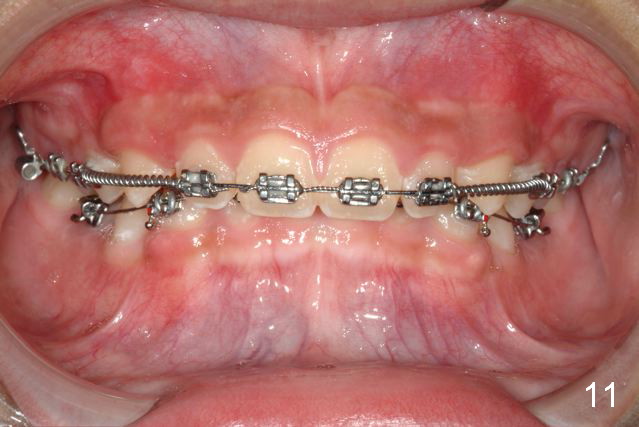

Brackets were placed on 2015_09_06 (Fig.11-13, Phase I pre-orthopedic tooth movement, leveling in advance of Herbst appliance therapy using ankylosed Es).   Six months later (Fig.14-16), LR7 did better, LL7 did not and will need intervention. But intrusion of L 3-3 looks good.